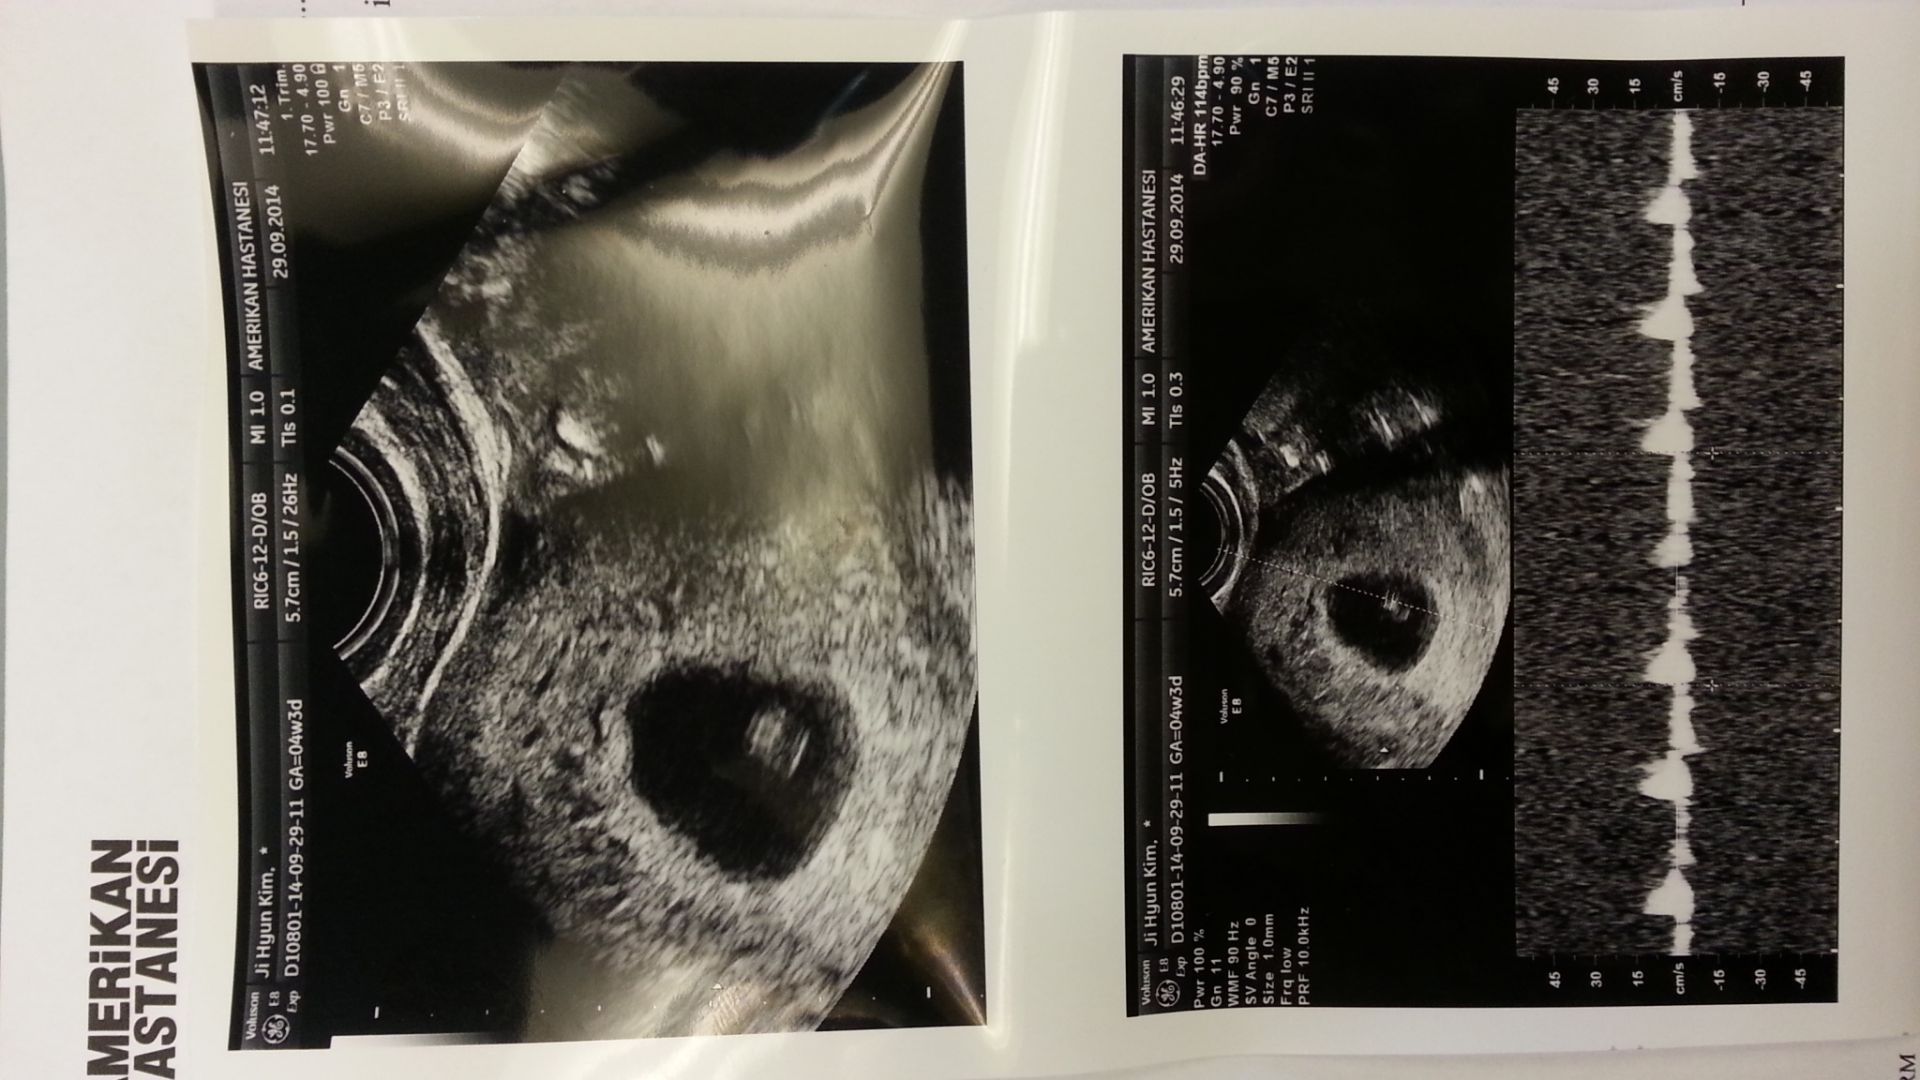

제가 드디어 엄마가 되는 소식이에요~!!!!

대통이가

(아이 태명이에요~)

요즘 입덧도 없고, 아프지도 않고,

엄마 몸상태도 생각해주면서 쑥쑥 자라고 있습니다.^^